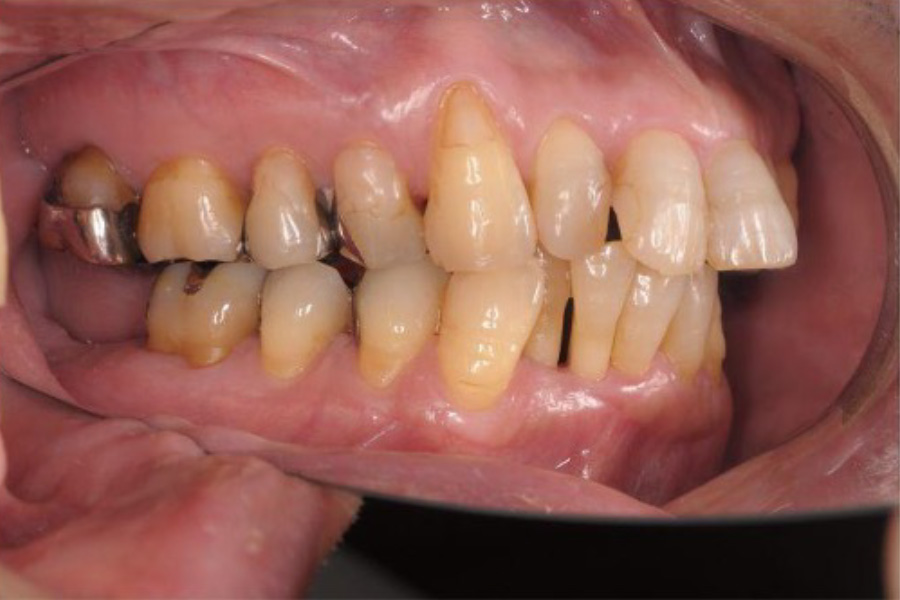

治療前

| 主訴 | 数年前から左下の一番奥の歯が噛んだときに痛む。 通院していた歯科で痛みはとれないがまだ抜かない方が良いといわれたが、ずっと痛いままなので不安になり来院。 |

| 治療内容 | 全顎治療:歯周病治療、抜歯、根管治療、 咬合治療・矯正治療、フルメタルクラウン(保険) |